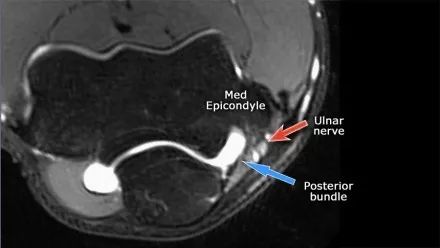

在研究韧带时,尤其是UCL,始终使用轴向图像。如果你看内侧上髁,你会发现后束是一个薄的结构(蓝色箭头)。注意在肘管内的尺神经。

后束形成肘管隧道的地板。支持带覆盖肘管。请注意,前束更厚(白色箭头)。您可以看到前韧带和后韧带之间的区别,即使它们形成一条韧带。走向远端,我们会看到它们合并在一起以附着于崇高的结节。